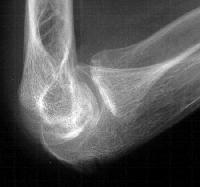

Five years later, he has limited motion (E/F 35/100) and painful clicking with elbow flexion and extension.

Plain films show humeral osteophytes and posttraumatic changes of the capitellum and radial head.